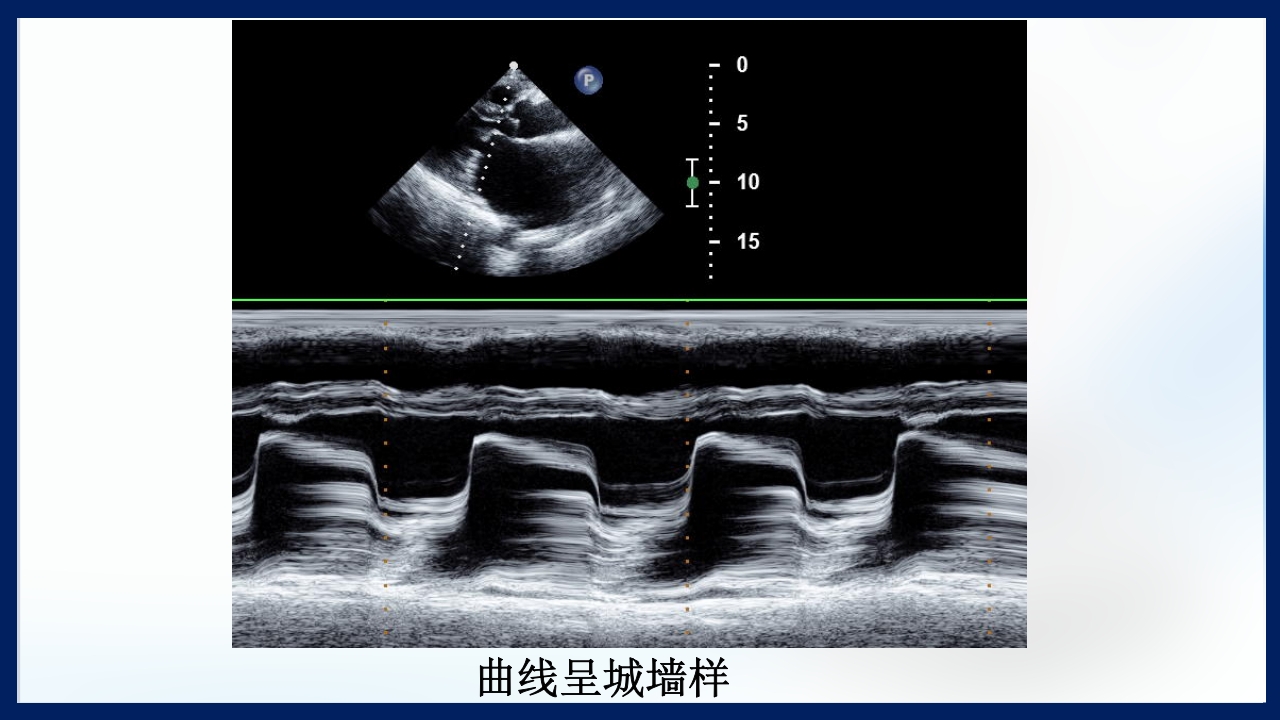

心 脏 瓣膜 医师:XXX 日期:20XX.XX.XX 讲授目的和要求 1 掌握二尖瓣和主动脉瓣膜病变的病理生理、临床表现及诊断方法。 熟悉二尖瓣和主动脉瓣膜病变的病因、鉴别诊断、并发症、治疗原则及 2 手术适应证。 3 了解瓣膜病的检查方法及治疗新进展。 心脏瓣膜病 是由于炎症、粘液样变性、退行性改变等原 因引起的单个或多个瓣膜结构的功能或结构异常,导致 瓣口狭窄及(或)关闭不全。二尖瓣最常受累,其次为 主动脉瓣。 (Rheumatic Heart Disease)简称风心病, 是风湿性炎症过程所致瓣膜损害,主要累及40岁以下人 群。 瓣膜粘液样变性和老年瓣膜钙化所致瓣膜病日渐增多。 3 瓣膜病分类 按病因分类: 风湿性、老年退行性、先天性、相对性 按受累部位和类型分: 二尖瓣狭窄、二尖瓣关闭...